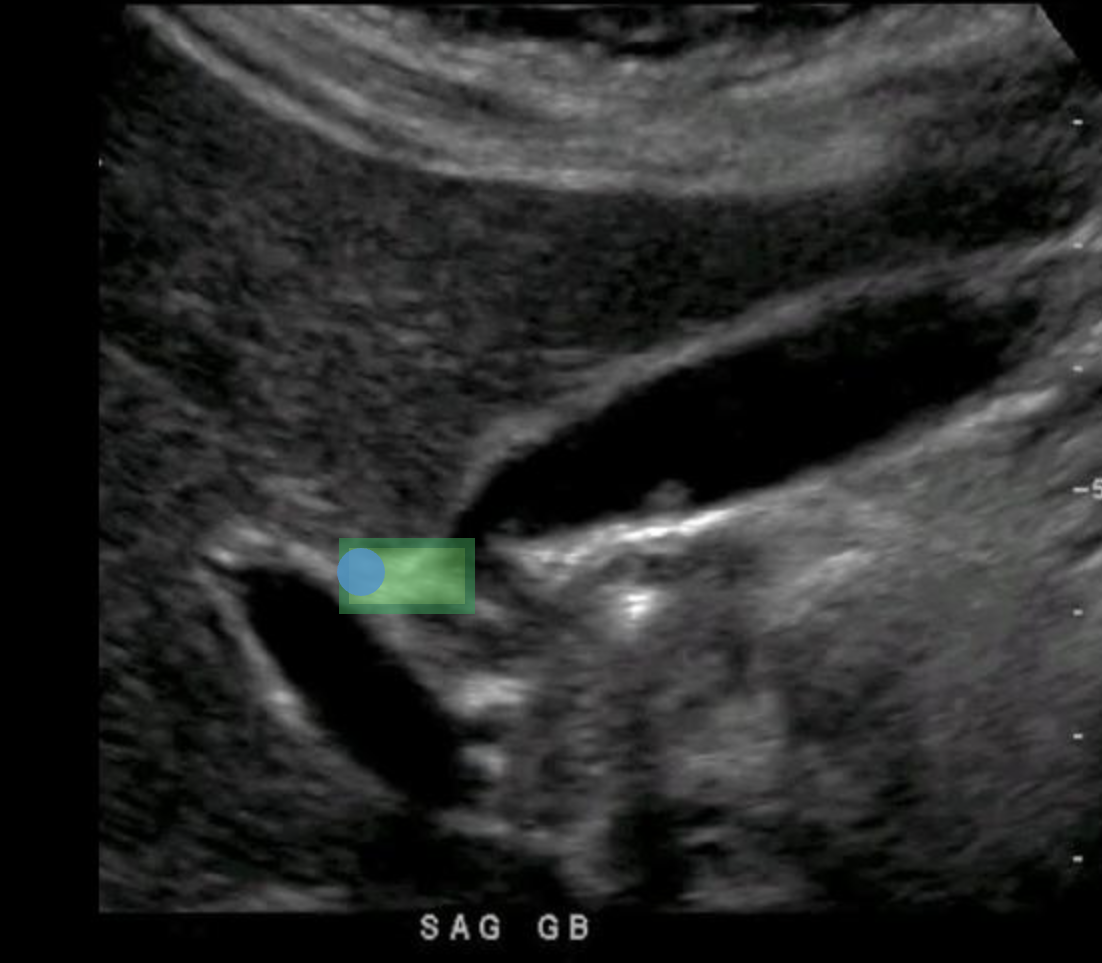

During an abdominal ultrasound, a 4mm circular anechoic structure is identified at the posterior portion of the pancreas head. Color flow is not identified in the structure. What is it?

common bile duct